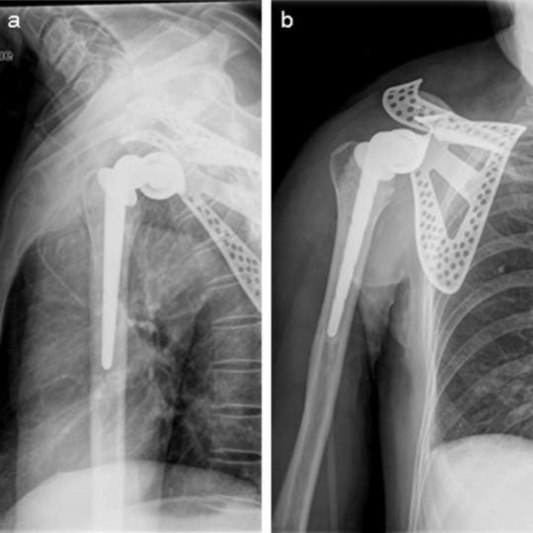

An artificial total shoulder was customized, and the operation of the right scapular tumor resection and tumor type with to wholly the scapula artificial shoulder arthroplasty and lesions lymph node including the pathological lymph node below right subclavian and above left supraclavicular dissection had been performed in March 2011 (Fig. 4 a, b). To achieve full exposure of scapular and tumor, scapular notch was implemented, approximately 2 cm of the distal end of right clavicle excised. Then the original tumor and the 3 cm area surrounding it together with whole right acromioclavicular joint was removed, followed by fixing biceps long head tendon to stump of clavicle and prosthesis installment. After discharge from our hospital, ten days of chemotherapy, combination of dacarbazine, pharmorubicin and cisplatin, was applied in patient in May 2011 in another hospital and given up due to anorexia and vomit. Right scapular mass, right submaxillary lymphadenectasis, and ascites were observed. Nodules in superior lobe of right lung and inferior lobe of left lung were observed in CT results (Fig. 5 a, b, c) which suggested potential pulmonary metastases in September 2011. Multiple organ failure caused the death of patient in November 2011.

Fig. 4.

Postoperative X-ray test. Images show that shoulder joint prosthesis is well placed.